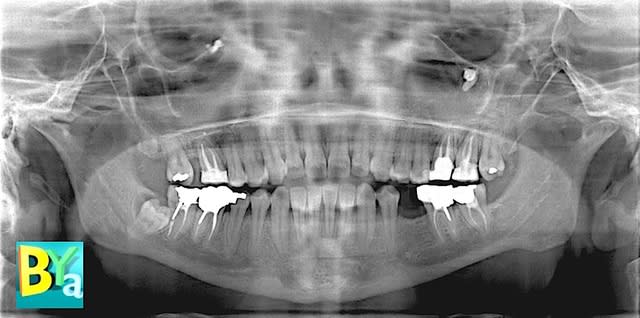

OSIRIX sur mac est un logiciel fantastique qui permet de voir vos scanners sous un angle que nous n'avons pas encore l'habitude de voir.

Il permet une étude en 2D

une étude en 3D volumique, mais comme c'est une visualisation par moteur de rendu interne, les images ne sont que du 2D à l'export.

une étude en 3D surfacique, une unité HOUNSFIELD est choisie pour la reconstruction surfacique, dont les modéles sont de la 3d et donc exportables en fichier 3D ce qui permet de les importer dans d'autres logiciels de 3D plus spécialisés dans la CAO comme BLENDER.

un clic sur 3d volumique et tu obtiens déjà l'image 2

c'est top tes images ! tu les as faite à partir d'un fichier Dicom d'un scanner ou d'un cone bean ?

ce sont des CT scan, mais ça marche aussi avec les CBCT.